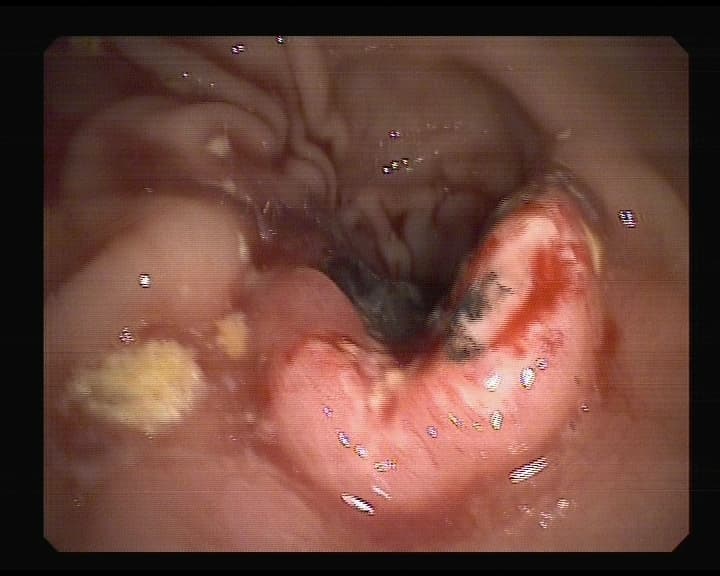

ÚLCERA GASTRODUODENAL.La Úlcera gastroduodenal o ÚLCERA PÉPTICA es una llaga que se forma en la capa que recubre...

DOCTOR, llevo varios meses con un dolor de estómago y el hombre se toca el centro del abdomen, entre ambas parrillas costales. ¿Tendré úlcera?La ÚLCER...